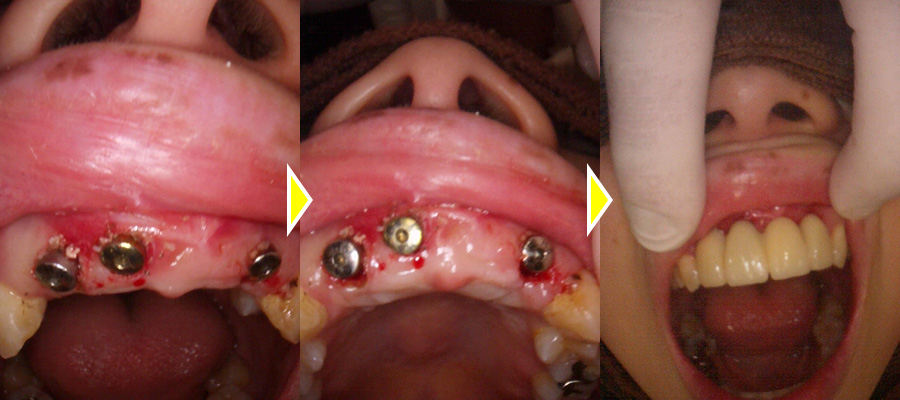

インプラント治療の実施

4歯を一度に抜歯後、膿を取り出したところ、範囲が大きく、骨を溶かしてしまっていたため骨に穴があいてしまっていることが実際に肉眼で確認できました。

穴があいているため骨補填材が骨外にはみ出てしまうことを防ぐため、歯肉剥離し、外側からも吸収性の膜を張り骨造成を行いました。

4歯を抜歯し、インプラント体の埋入を3本行い、4カ所の骨造成までを1度のオペにて行いました。

そして審美的に前歯が無くなる事がないように治療用義歯を即日セットし終了しました。

1ヶ月後の抜糸の際に治療用義歯の内面を歯茎に合わせて調整を行いました。

それによりフィット感が増し違和感が減りました。

上部構造(人工歯)の装着・治療完了

オペから5ヶ月待機し、CTにて骨の状態を確認し、二次オペを行いしっかりと骨とインプラントがくっついている事を確認できました。

型取りを2回行い、上部構造を作成、セットしました。

審美的にも機能的にも大変満足していただいています。